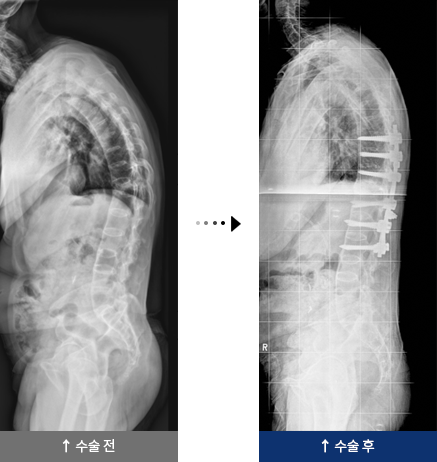

결핵성 후만증